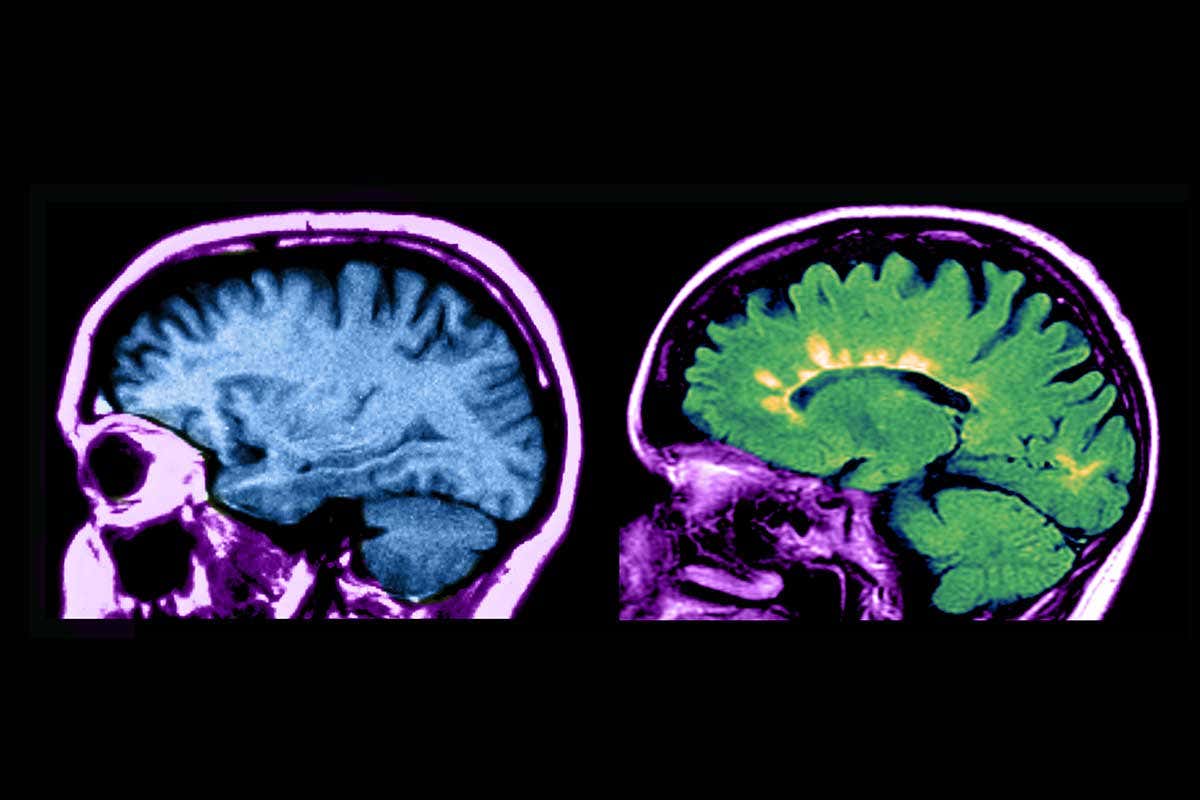

MRI scans of a healthy brain (left) and one with multiple sclerosis (right) Jessica Wilson/Science Photo Library

In multiple sclerosis, the immune system attacks the protective coating around nerve cells in the brain, spinal cord and optic nerves. It tends to come and go in flare-ups that get worse over time, and can eventually leave people paralysed and blind. Existing drug treatments can lessen the severity or frequency of attacks but are not a cure and don’t work for some.